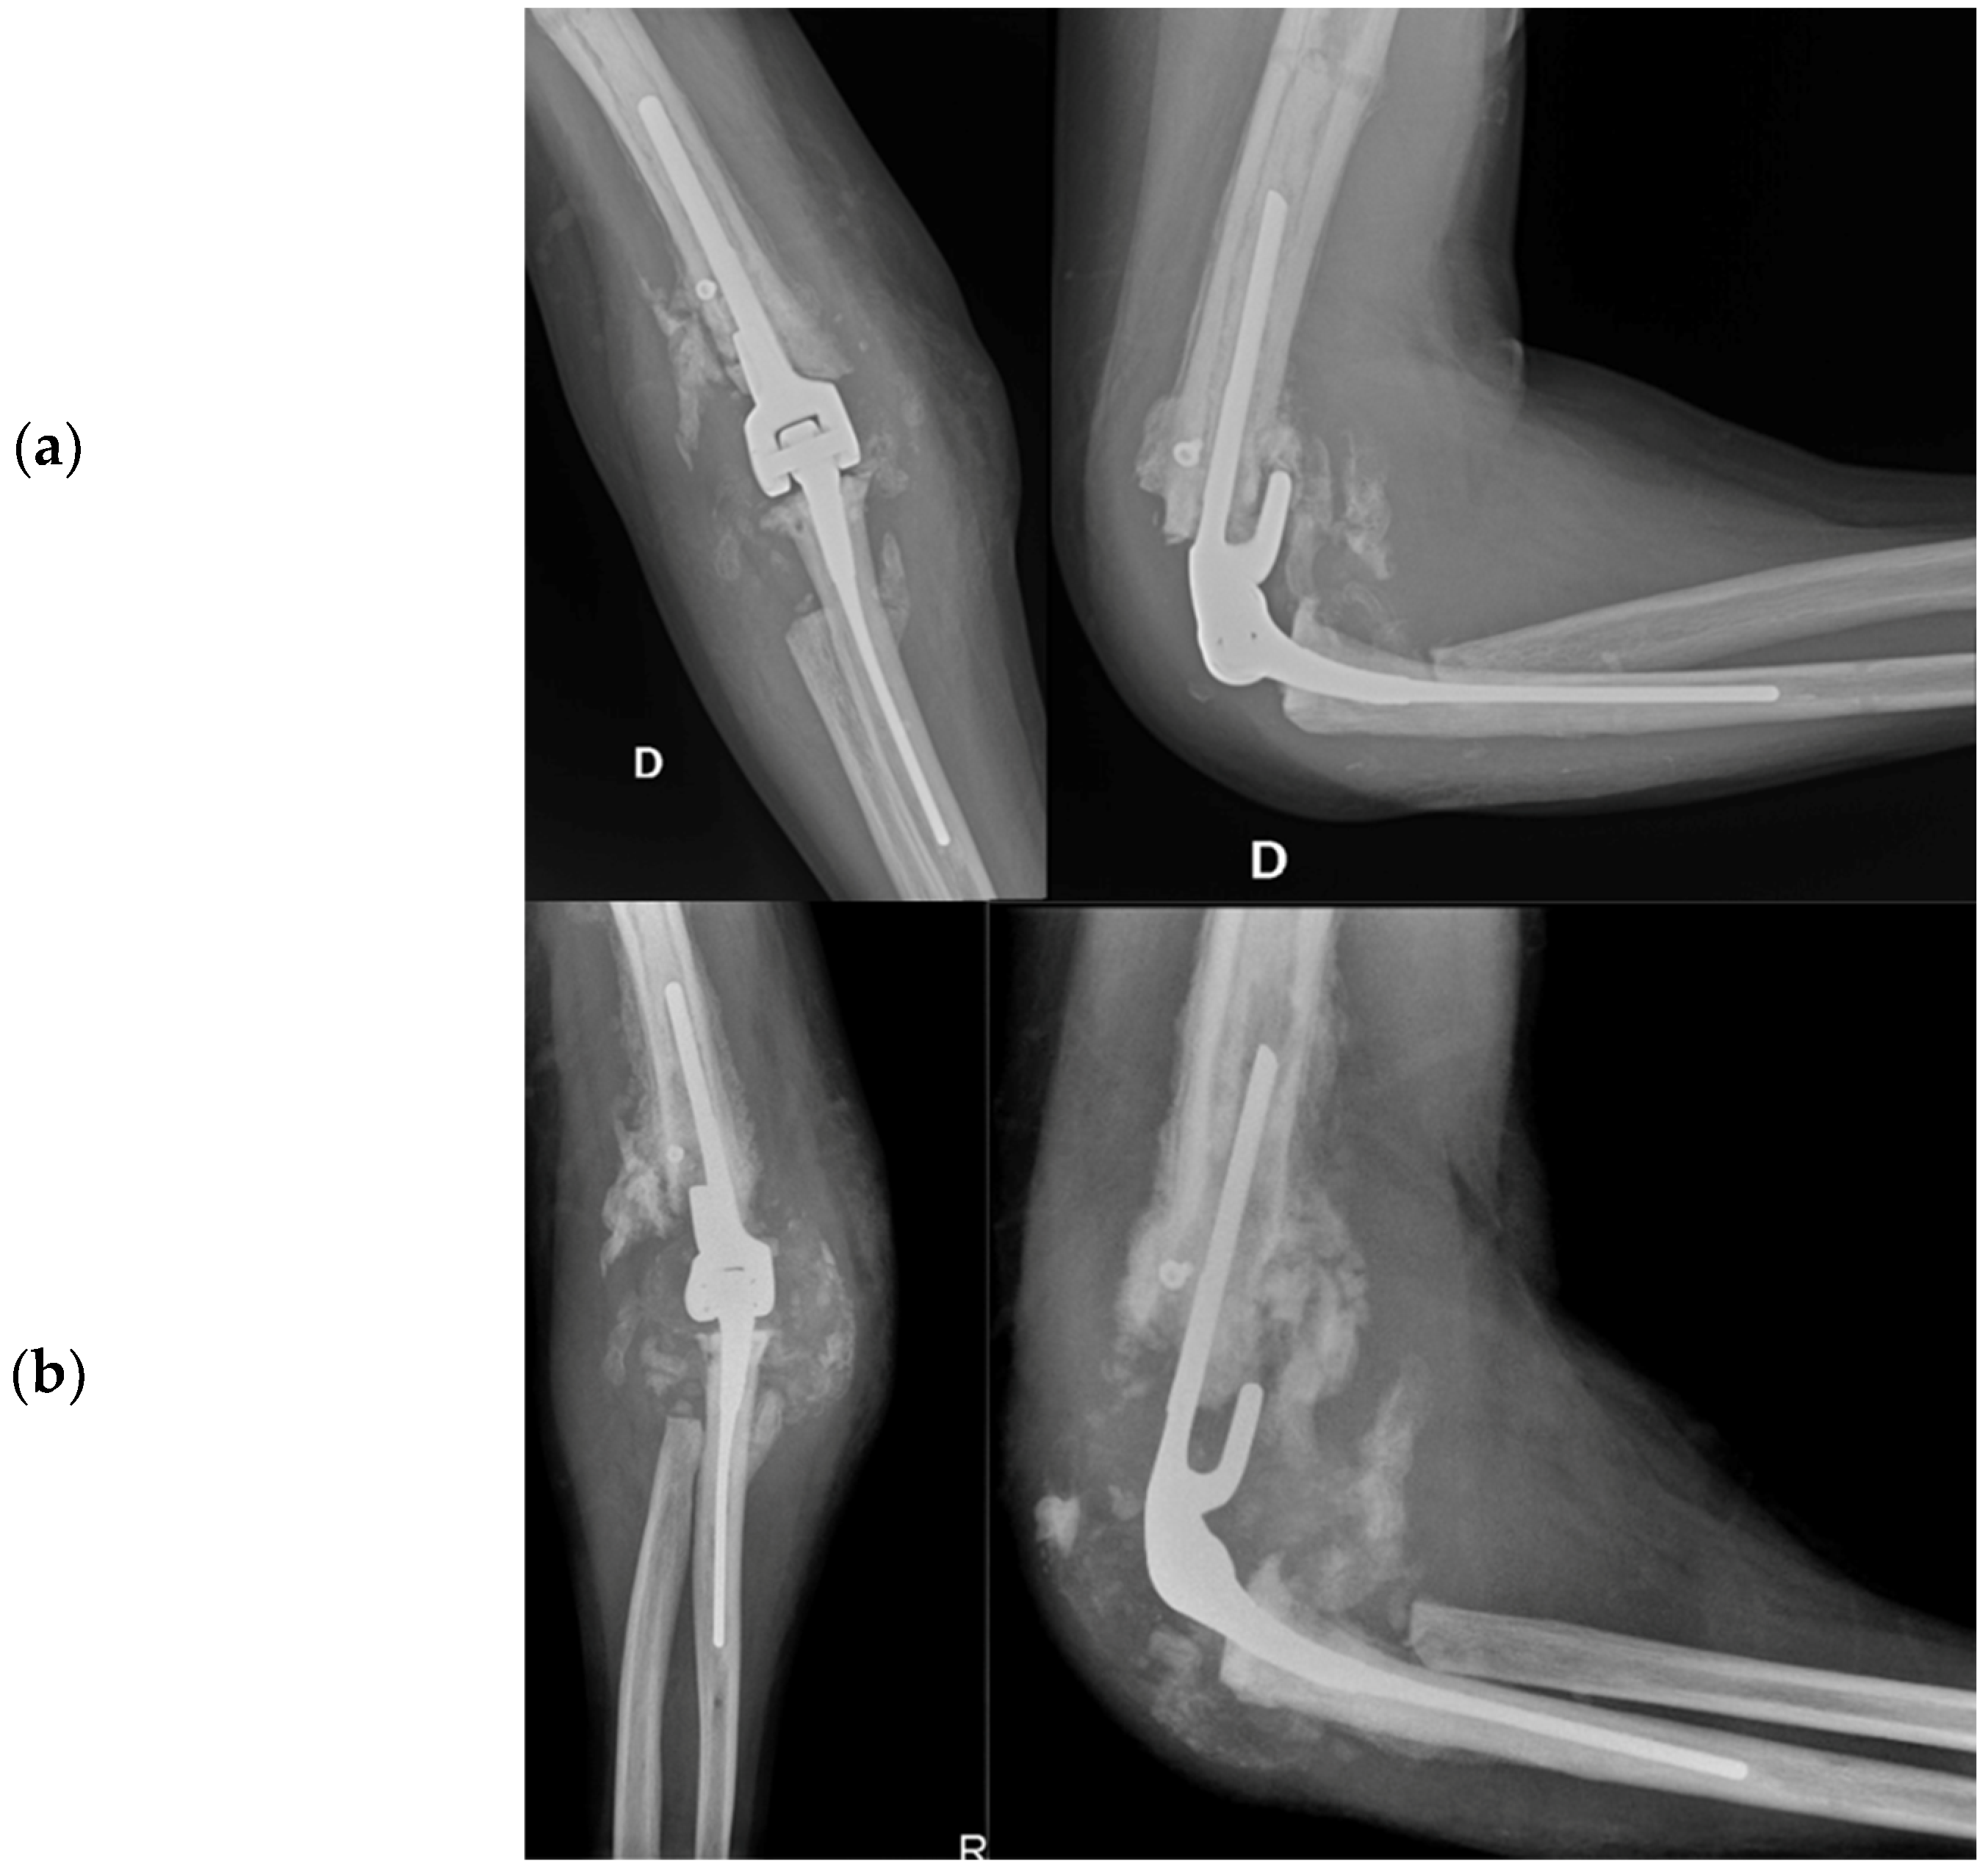

2.4.5. Total Elbow Arthroplasty

- Evidence from the Scientific Literature

Total Elbow Arthroplasty and Complications